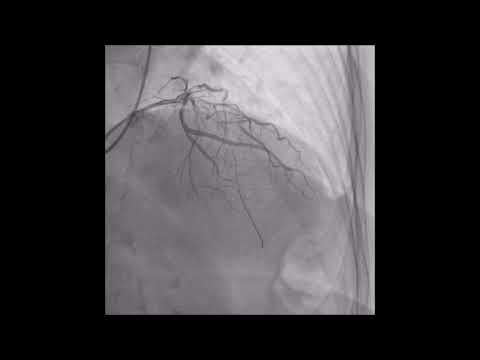

Angiography of the Left Main Coronary Artery